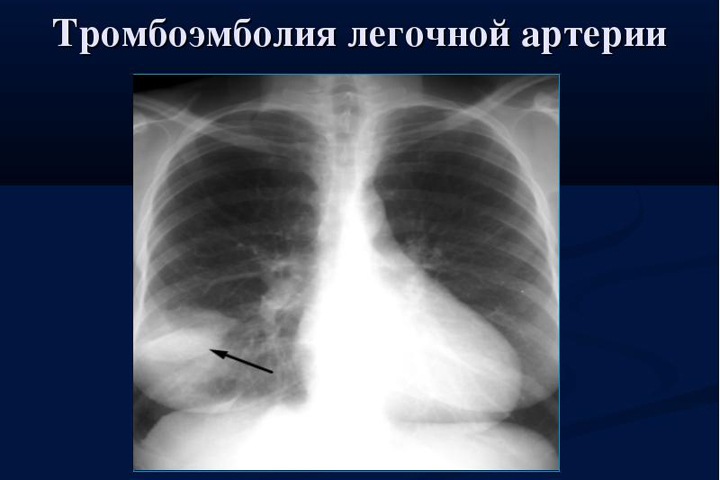

Врачи сделали операцию мужчине 73 лет. Он перенес тромбоэмболию — болезнь, при которой образуются кровяные пробки в сосудах. Если после снятия острого состояния кровоток в легких не восстанавливается полностью, заболевание переходит в хроническую форму — ее можно вылечить только хирургическим удалением застарелых сгустков из артерий, из-за чего кровь не доходила до легких в нужном объеме. Пациент почти не мог двигаться, а любая нагрузка вызывала головокружение, сообщает краевой минздрав.